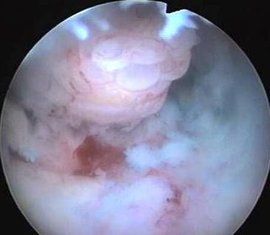

子宮頸息肉多由於長期慢性炎症的刺激,使子宮頸管黏膜增生形成息肉,形狀如水滴,由子宮頸口突出,顏色鮮紅,質軟而脆,觸之易出血。一個或多個不等,直徑一般在1cm以下,蒂細長,根部多附著於子宮頸外口,少數在子宮頸管內。由於炎症存在,除去後常可復發。

另外,還有一種來自子宮頸陰道部的息肉,質較硬韌,表面被覆鱗狀上皮,外觀呈粉色,觸之不易出血。